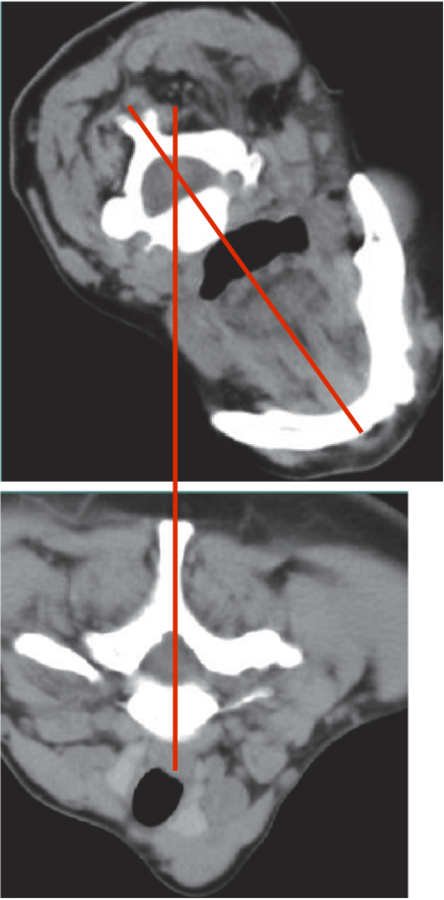

LATEROCOLLIS

Larynx shifted relative to sternum

LATERAL SHIFT

Secondary to lateral flexion of the spine and flexion of the head in the opposite direction.

Line from Sternum to larynx